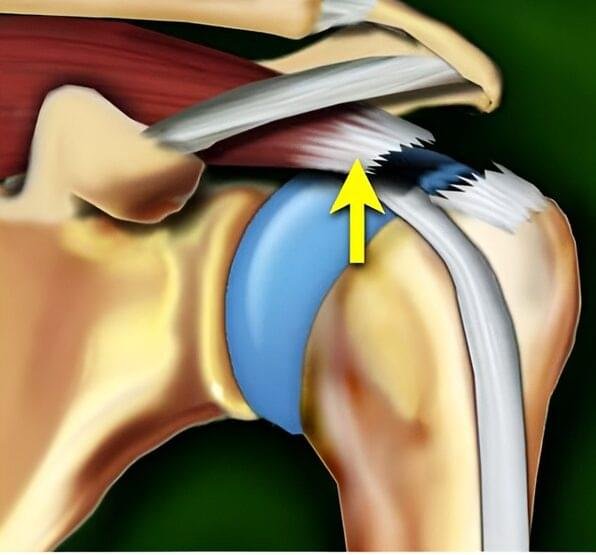

In addition to enabling arm movement, the rotator cuff muscles have an even more important role — stabilizing the humeral head within the glenoid during motion. When stabilization is inadequate, the humeral head may shift upward toward the acromion during arm elevation. This can lead to irritation and injury of the shoulder tendons and bursae.

Bone spurs, particularly those located on the underside of the acromion, can contribute to the development of shoulder impingement syndrome. During arm elevation, the tendon may rub against the bone. If this impingement becomes chronic, it leads to increased tendon wear and may ultimately result in a rotator cuff tear.

The damage occurs on the upper (bursal) side of the tendon, which is in contact with the subacromial bursa. These tears are less common than intrasubstance tears and articular-sided tears. They are often associated with shoulder impingement, where the tendon rubs against the undersurface of the acromion during shoulder movement. The presence of bone spurs (osteophytes) on the inferior surface of the acromion is considered a risk factor, as they may mechanically irritate the tendon. - Articular-sided tear